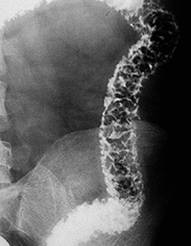

Examenul baritat cu dublu contrast evidentiaza ulceratiile aftoide sub forma unor mici depozite de substanta de contrast inconjurate de un halo transparent. Mai pot fi evidentiate leziuni unice sau multiple despartite de zone sanatoase- aspectul de "pietre de pavaj", stenoze pana la "semnul sforii", fistule. Cand exista suspiciunea de stenoza, examenul baritat este contraindicat.

Boala Crohn- ulceratii extensive Semnul

sforii in boala Crohn

ale peretelui colonului, inflamatia mucoasei ileala